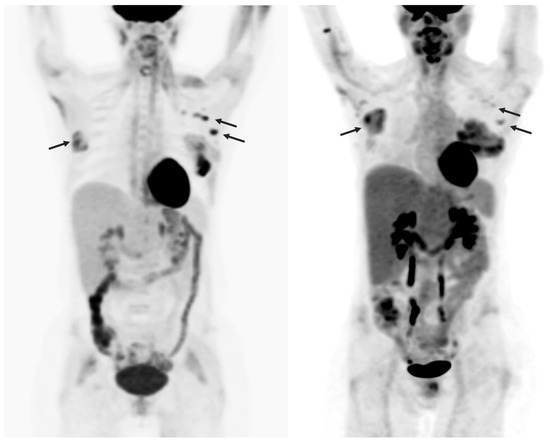

Rarely, CRS cytokines can induce hemophagocytic lymphohistiocytosis (HLH), a severe immune response that induces liver dysfunction [71]. It is diagnosed using CT, PET/CT, biopsy, and ultrasound. Care is mainly supportive, with steroid immunosuppressive agents in severe cases [71] (Figure 6).

Figure 6.

A 47-year-old woman with acute lymphoblastic leukemia and remote history of melanoma. Maximum intensity projection images pre- (left) and post- (right) CAR T-cell therapy showing new hepatomegaly with mild increased heterogeneous FDG uptake, with mixed changes in extramedullary leukemic involvement, increased in the right breast and decreased in the left axillary nodes.